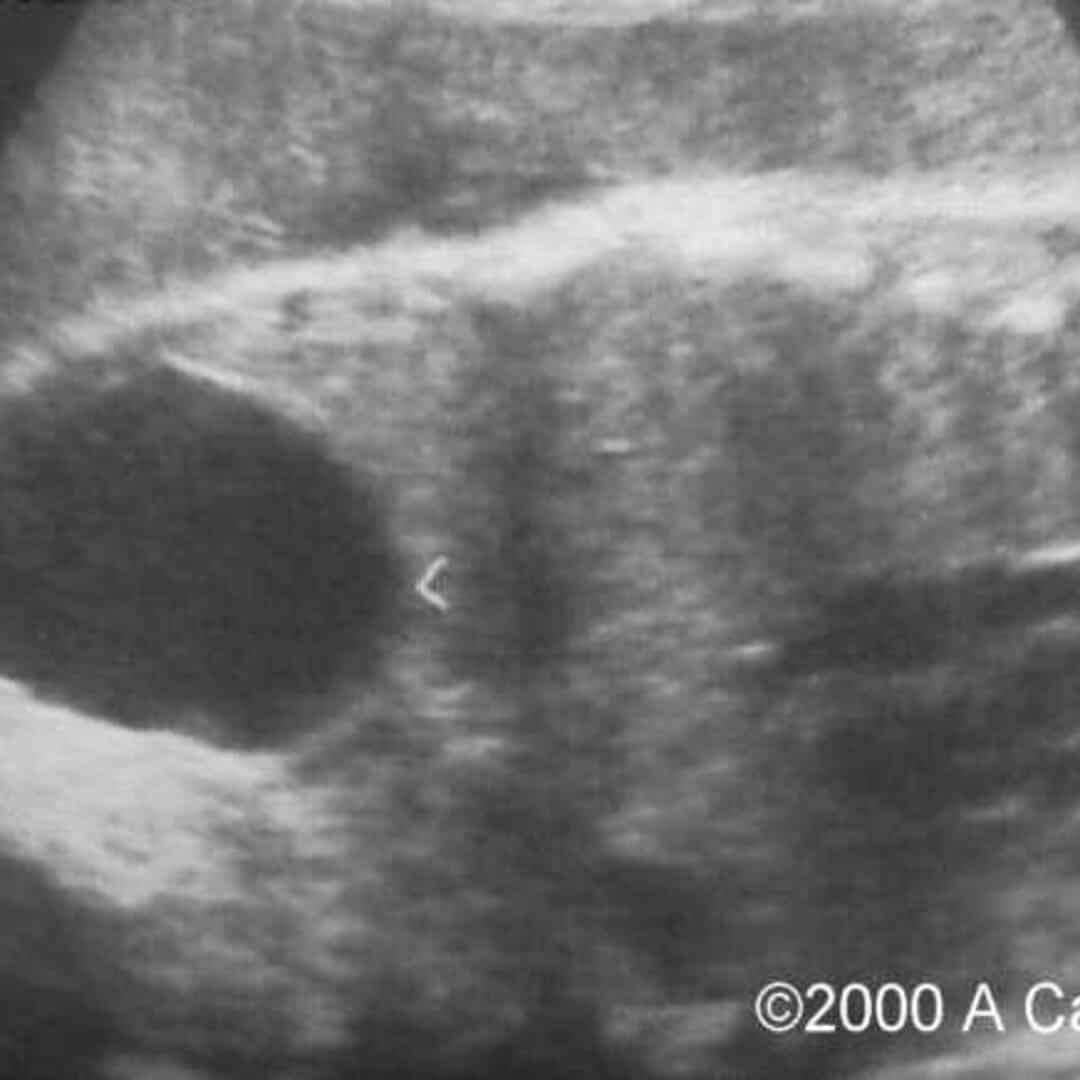

from thefetus.net

📃 Ovarian cyst, torsion

📃 Ovarian cyst, torsion Chocolate Cyst Torsion They are filled with dark brown endometrial fluid and are sometimes referred to as chocolate cysts. the presence of. An ovarian endometrioma is a cyst that’s filled with the same fluid that’s in the lining of your uterus (endometrium). Endometriomas are also called chocolate cysts because they are filled with dark brown menstrual blood. Here, learn about the treatments for. Chocolate Cyst Torsion.